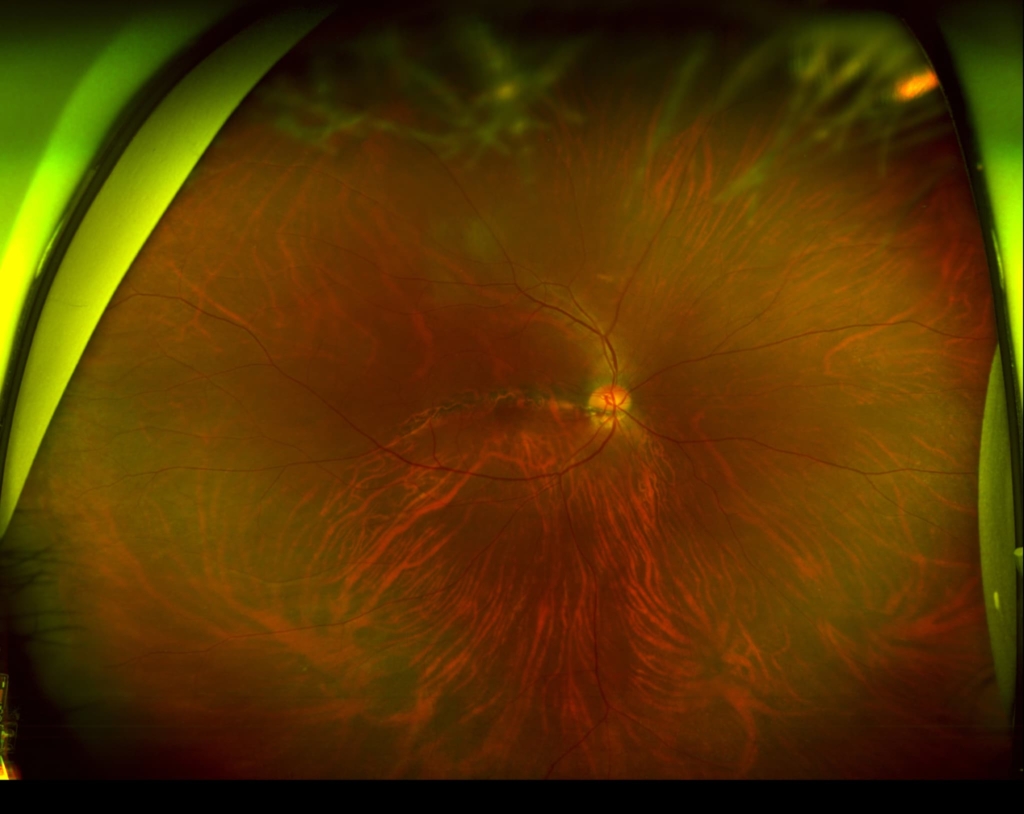

乳頭が下鼻側に傾斜し、下方に萎縮(PPA)がみられる。

両眼ともに、後部ぶどう腫staphylomaの上縁に一致して乳頭下縁から黄斑を横断するように帯状の網脈絡膜の萎縮巣がみられる。また後部ぶどう腫領域に一致して網膜・脈絡膜が菲薄化しているため、紋理眼底tessel lated fundusがみられる。